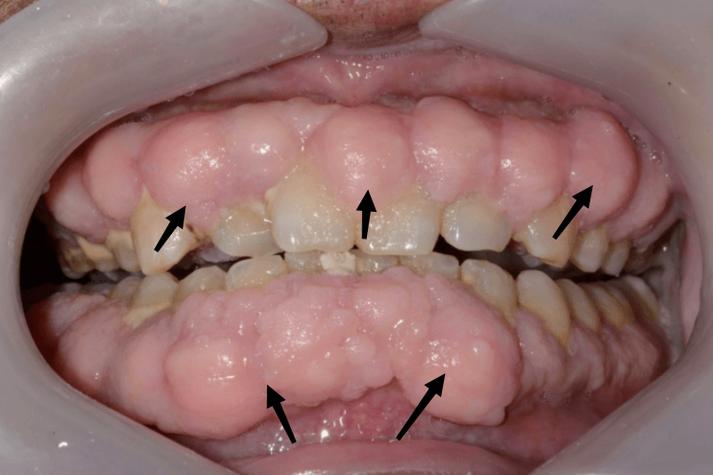

牙龈增生的临床表现主要包括:牙龈乳头和牙龈边缘明显肿胀,呈球形或分叶状,表面光滑或呈颗粒状;颜色从鲜红到暗红不等,质地松软易出血;严重时可增生至牙齿切缘或咬合面,影响美观和咀嚼;部分患者伴有口臭、牙龈疼痛或刷牙时出血症状。